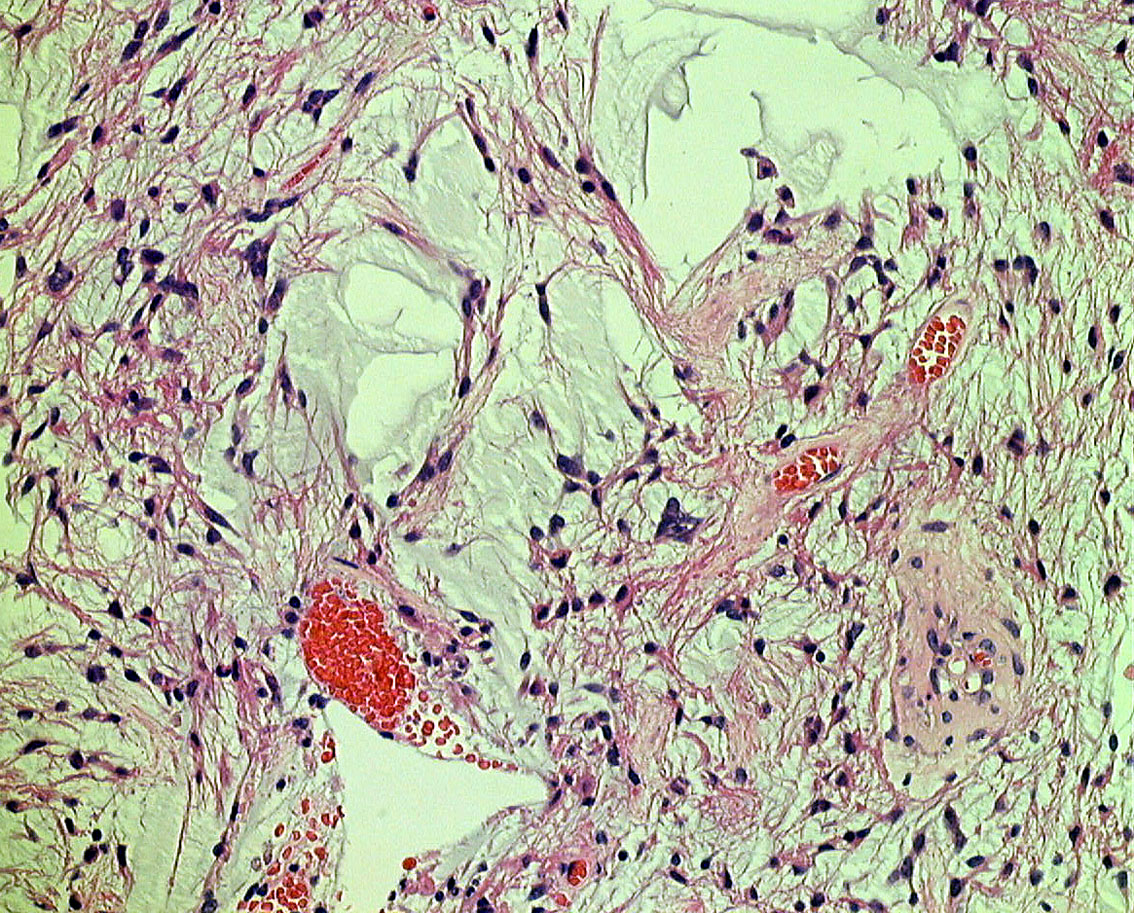

10才小児の小脳結節性毛様細胞性星細胞腫です。典型的な良性腫瘍として知られる毛様細胞性星細胞腫です。

HE染色です。左のように双極性突起を延ばす小型の核を有する充実性部分 compact part と,中央に見られるような細胞間に微小嚢胞変性と類粘液性基質がみられる海綿状部分 spongy partが混在する毛様細胞性星細胞腫に特徴的なbiphasic patternがみられます。右側の画像では小さな粘液基質を含みながらびまん性星細胞腫に類似する組織像が認められます。左の画像の矢印で示す赤い玉のようなものはeosinophilic granular bodiesです。

左がS100,中央がGFAP,右がMIB-1 (Ki-67)染色です。MIBはやや高値で3%と報告されました。病理組織診断は,WHO grade 1 毛様細胞性星細胞腫です。